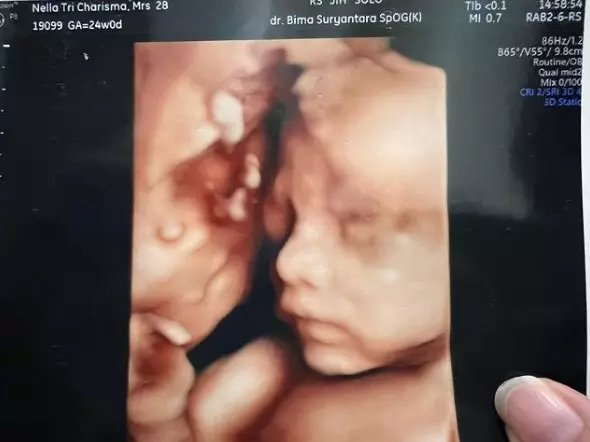

Hasil USG tersebut dibagikan Nella melalui Instagram pribadinya @nellakharisma pada Selasa (20/12). Hasil USG model 3D itu memperlihatkan wajah mungil anak kedua Nella dan Dory. Mulai dari bentuk kepala, mata, hidung, sampai bibir, terlihat begitu jelas.

foto: Instagram/@nellakharisma